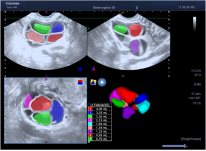

* 多切面显示模式&STIC模式:

* 自动容积测量功能:通过识别无回声/极低回声区域的轮廓来自动计算容积。临床可用于卵泡的计数,监测排卵等。